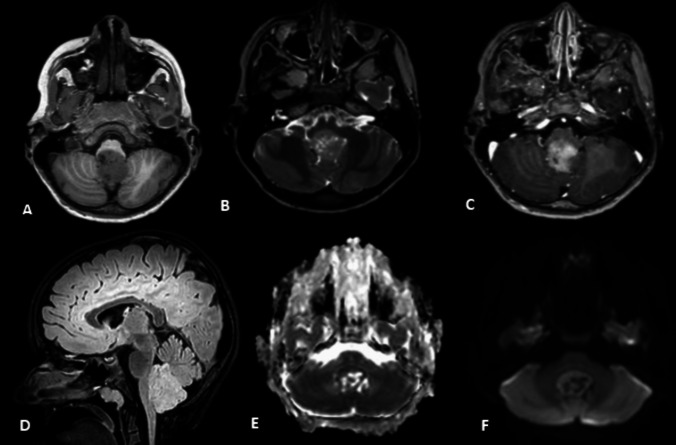

A 7-year-old boy presented to the hospital with recurrent nausea and vomiting over 2 weeks. A cranial MRI revealed a large heterogeneous lesion in the posterior fossa extending from the fourth ventricle to the foramen magnum with contact to the brainstem. The lesion showed moderate diffusion restriction and multiple small cystic components. The child underwent gross total resection. The primary histological findings suggested proliferative active tumor without further definition. The extended histological examination 3 weeks later confirmed the diagnosis of astroblastoma. Due to complete resection and full recovery of the patient, watchful waiting with radiological follow-up was recommended. Astroblastoma is an extremely rare tumor especially in the posterior fossa. However, it should be considered as a differential diagnosis in every tumor presenting the discussed radiological and histological features, especially in young aged patients.